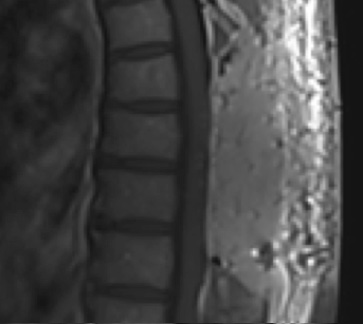

Postoperative MRI T2 illustrating the restoration of CSF surrounding the cord (blue arrow)